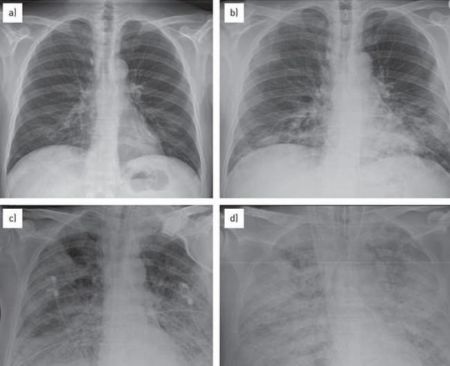

秋冬季节本就是北美流感高发季节,但2023年冬天似乎有些不寻常,一种“白肺”疫情正在悄然蔓延,已经在美国爆发,引发一波儿童肺炎感染浪潮!据外媒报道,美国有两个州现在儿童感染肺炎的病例正在激增,已经让医生们开始担心,这股疫情会扩散开来。

距离俄亥俄州辛辛那提郊外仅30英里的沃伦县,现在已经有142宗确诊“白肺综合症”的儿童病例,且一直在攀升,当地卫生官员表示这个数字已经“极高”。多个学区都接连出现确诊病例,响起警报。本周三,卫生官表示:“这不仅高于本地的平均水平,且符合俄亥俄州卫生部对疫情的定义。”

俄亥俄州卫生部门正在调查究竟是什么引发了疾病浪潮,疫情爆发的地区人口有200万左右,目前大部分患者都是儿童,平均年龄在8岁左右,有的孩子只有3岁。经检测,许多确诊儿童的肺炎支原体、链球菌和腺病毒检测都呈阳性。大多患者都有发烧、咳嗽、疲劳的症状,目前尚不清楚有没有出现死亡病例。